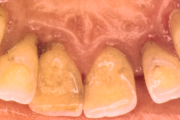

Krooniline parodontiit

Krooniline parodontiit on mikroobide poolt põhjustatud hammaste tugikudede põletik, mille tulemusena tekib progresseeruv alveolaarluu (nähtav röntgenograamil) ja periodontaalligamendi destruktsioon, igemetaskute moodustumine, igeme retsessioon või mõlemad kahjustused kombineeritult. Loe edasi »

- igemed punetavad (21)

- ige on paistes (mädapunn)

- igemed on tursunud/vohavad (17)

- puudulik suuhügieen (5)

- igemepealne hambakivi (5)